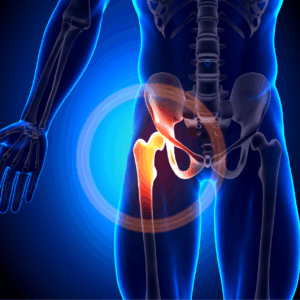

The hip is a ball-and-socket joint designed to move smoothly. Over time, different conditions can damage the protective cartilage in the joint, causing pain, stiffness and reduced movement. Conditions can include;

• Osteoarthritis

• Rheumatoid arthritis

• Avascular necrosis

• Hip fractures or injuries